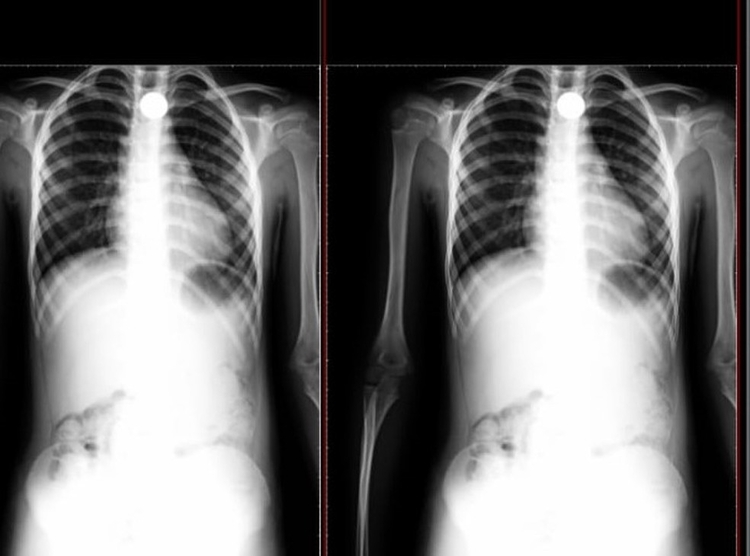

Segundo o G1, o menino de 8 anos chegou perto do pai e contou que havia engolido a moeda, e já mostrou sinais de falta de ar, o que preocupou a família, que levou a criança com urgência para um hospital, onde foi confirmado através de um raio-x, a existência do material.